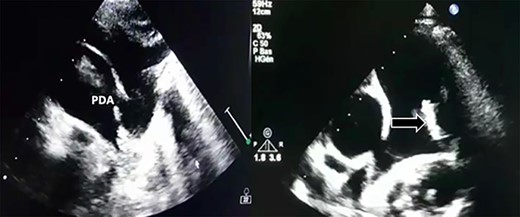

Transthoracic echocardiography revealed a large PDA (10 mm) with left-to-right shunt and a fixed structure on the wall of the pulmonary artery, with erratic movement indicative of a vegetation (Fig. 1), and mobile vegetation attached to the wall of the descending aorta in the supra-sternal view (Fig. 2) and a left ventricle with conserved systolic function and 55-mm end-diastolic diameter.

Large PDA and a fixed structure on the wall of the pulmonary artery.